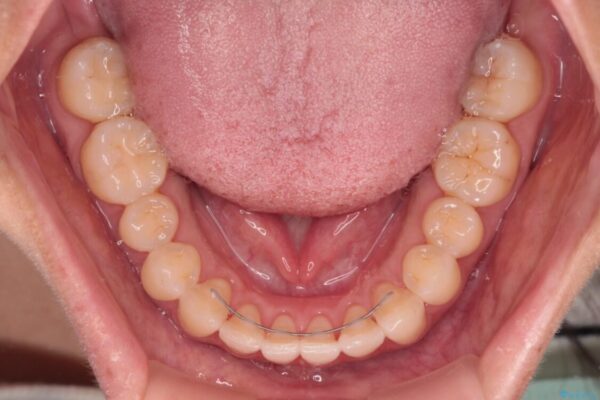

装着時間を守ってくださったので、予定通りの期間で終えることができました。インビザライン特有の、奥歯の咬み合わせの問題もなく、しっかりと歯列を改善することができました。

治療後

• 【モニター】前歯のデコボコをインビザラインで改善 治療後画像